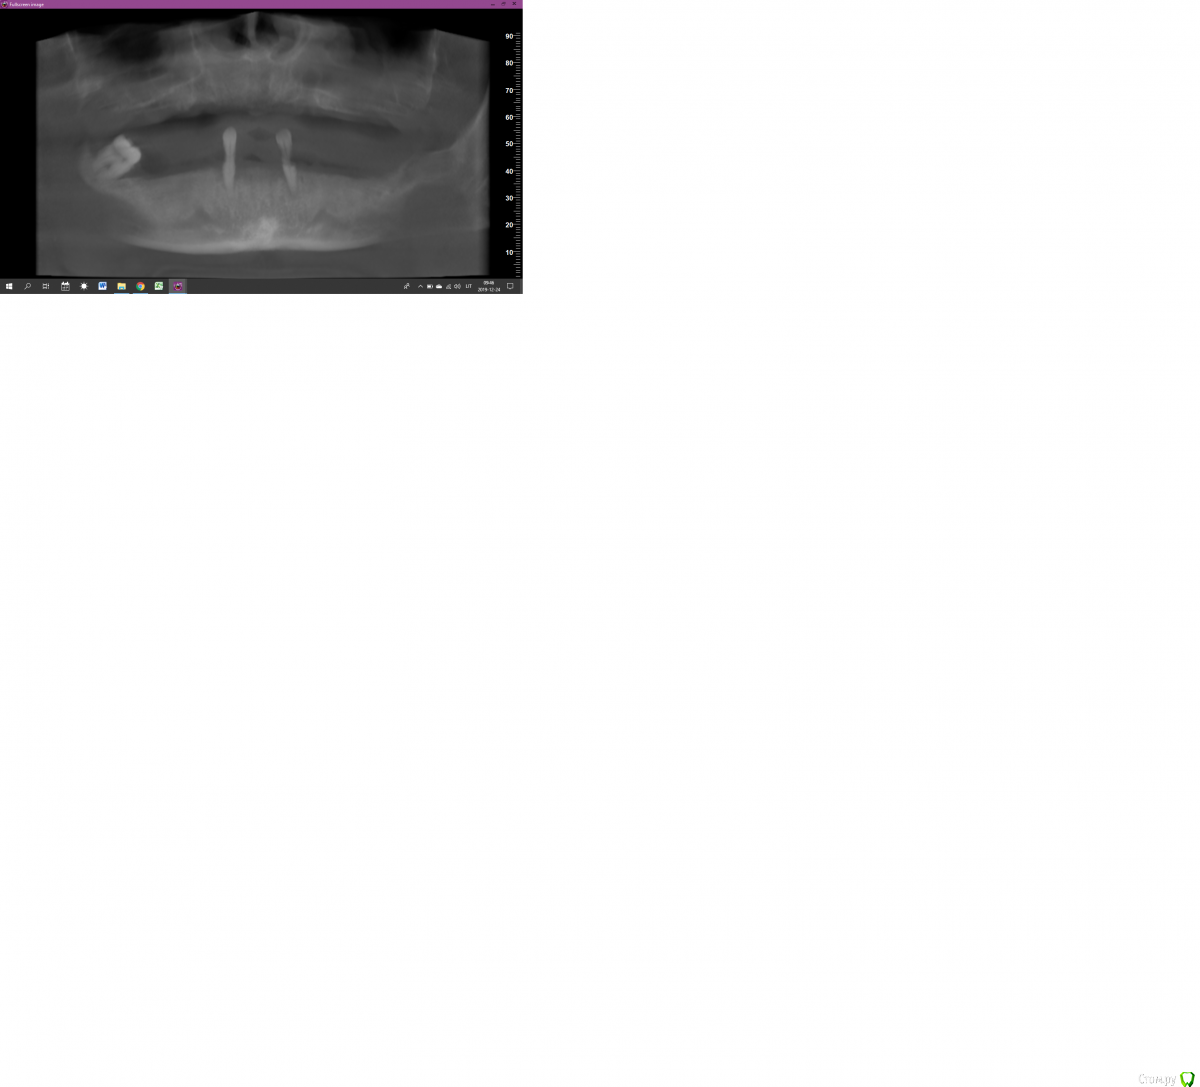

Lostikas Опубликовано 24 декабря, 2019 Поделиться Опубликовано 24 декабря, 2019 (изменено) Всех с наступающими праздниками! Коллеги прошу помогите разобраться с планом лечения. Полная реабилитация рта на имплантах, вопрос по поводу в/ч Возможно ли провести не большой закрытый синус лифт в области 15 зуба(1-2мм) и 25 зуба (1-2мм) при данном состоянии пазух особенно левой. лифт на сгустке без графта. если нет тогда план такой?: 4 импланта боковые под углом(класический ол он 4) далее к лору привести в порядок пазухи и через пару месяцев добавит в обости15-16 и 25-26? Спасибо! 2 фото область 25 зуба3 фото 15 Изменено 24 декабря, 2019 пользователем Lostikas Ссылка на комментарий

Bier Опубликовано 26 декабря, 2019 Поделиться Опубликовано 26 декабря, 2019 Олег а как бы вы поступили в данной клинической ситуации? справа там 8мм, слева 10? Поставил бы без синуса туда TL Ссылка на комментарий